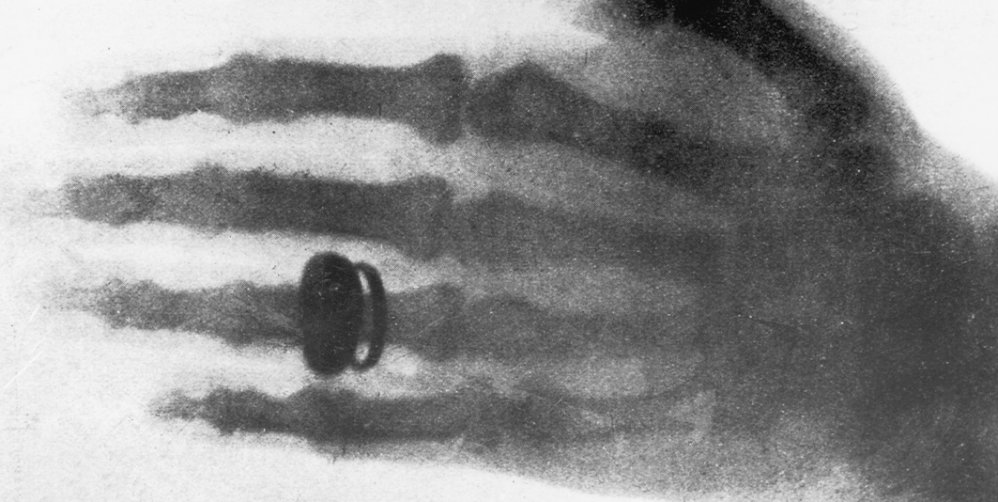

C’est en 1895 que le physicien allemand Wilhelm Röntgen a découvert la radiographie par hasard lors de ses expérimentations. Pour son premier test, il a fait une radiographie de la main de sa femme. La diffusion de cette image a déclenché un véritable engouement au sein de la communauté scientifique et médicale.